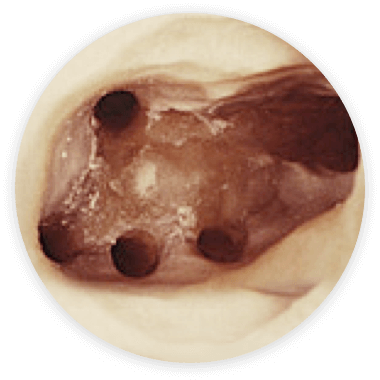

Mit Hilfe des Mikroskops ist es heute möglich verblockte Kanaleingänge und Kanalabgänge in der Tiefe zu erkennen und unter Sicht zu behandeln.

In vielen Fällen verfügen die Zähne über mehr Wurzelkanäle als mit dem bloßen Auge oder auch der Lupenbrille zu erkennen sind.

So haben obere Backenzähne zu 95 % einen zusätzlichen Kanal, der nur in den seltensten Fällen ohne mikroskopische Hilfe zu behandeln ist.